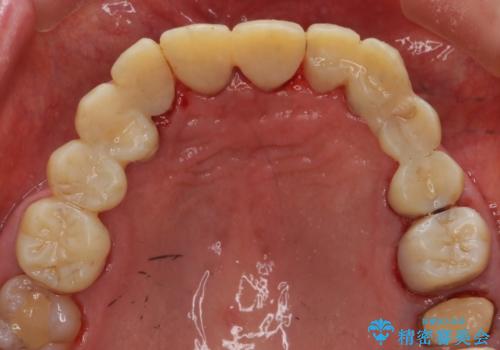

ステインがたくさん付着していたので、エアフローを用いてステインを除去しました。そのため、直後の写真は歯肉からの出血が見られます。

まず歯石取りを行い歯肉の状態を改善後、後日PMTC30分コースをしました。